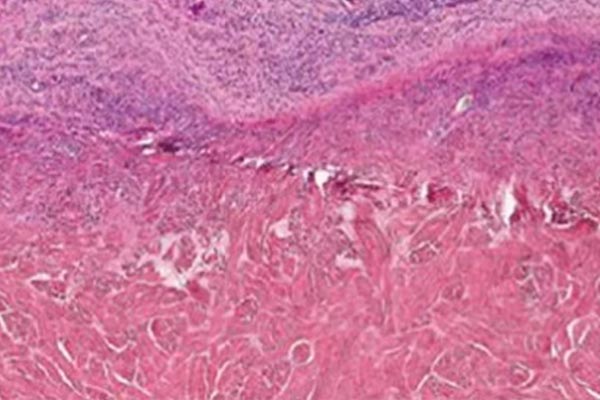

HISTOLOGY

5 x magnification, highlighting the Collagen fibres of the matrix. Note Absence of cellular material

Histology demonstrating the remodeling process of Native® porcine matrix. In the upper part infiltration of fibroblasts and rich neovascularization can be seen